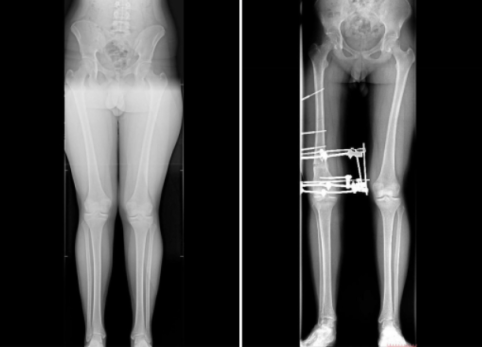

В Самарской области парень не мог жить полноценной жизнью из-за особого ног. 16-летний подросток страдал от вальгусной деформации - она вызывала сильную боль в коленях и вынуждала отказываться от занятий спортом. Кроме того, его смущал внешний вид ног.

На помощь пришли врачи Клиники СамГМУ. Ситуация оказалась непростой: деформация имела асимметричный характер, а одну из конечностей требовалось немного удлинить. Медики приняли решение проводить коррекцию поэтапно: сначала прооперировать одну ногу, потом вторую.

В начале декабря юноше сняли аппарат внешней фиксации. Сейчас он уже проходит реабилитацию и постепенно возвращается к обычной жизни. По словам врачей СамГМУ, без лечения у подростка мог развиться артроз коленного сустава.